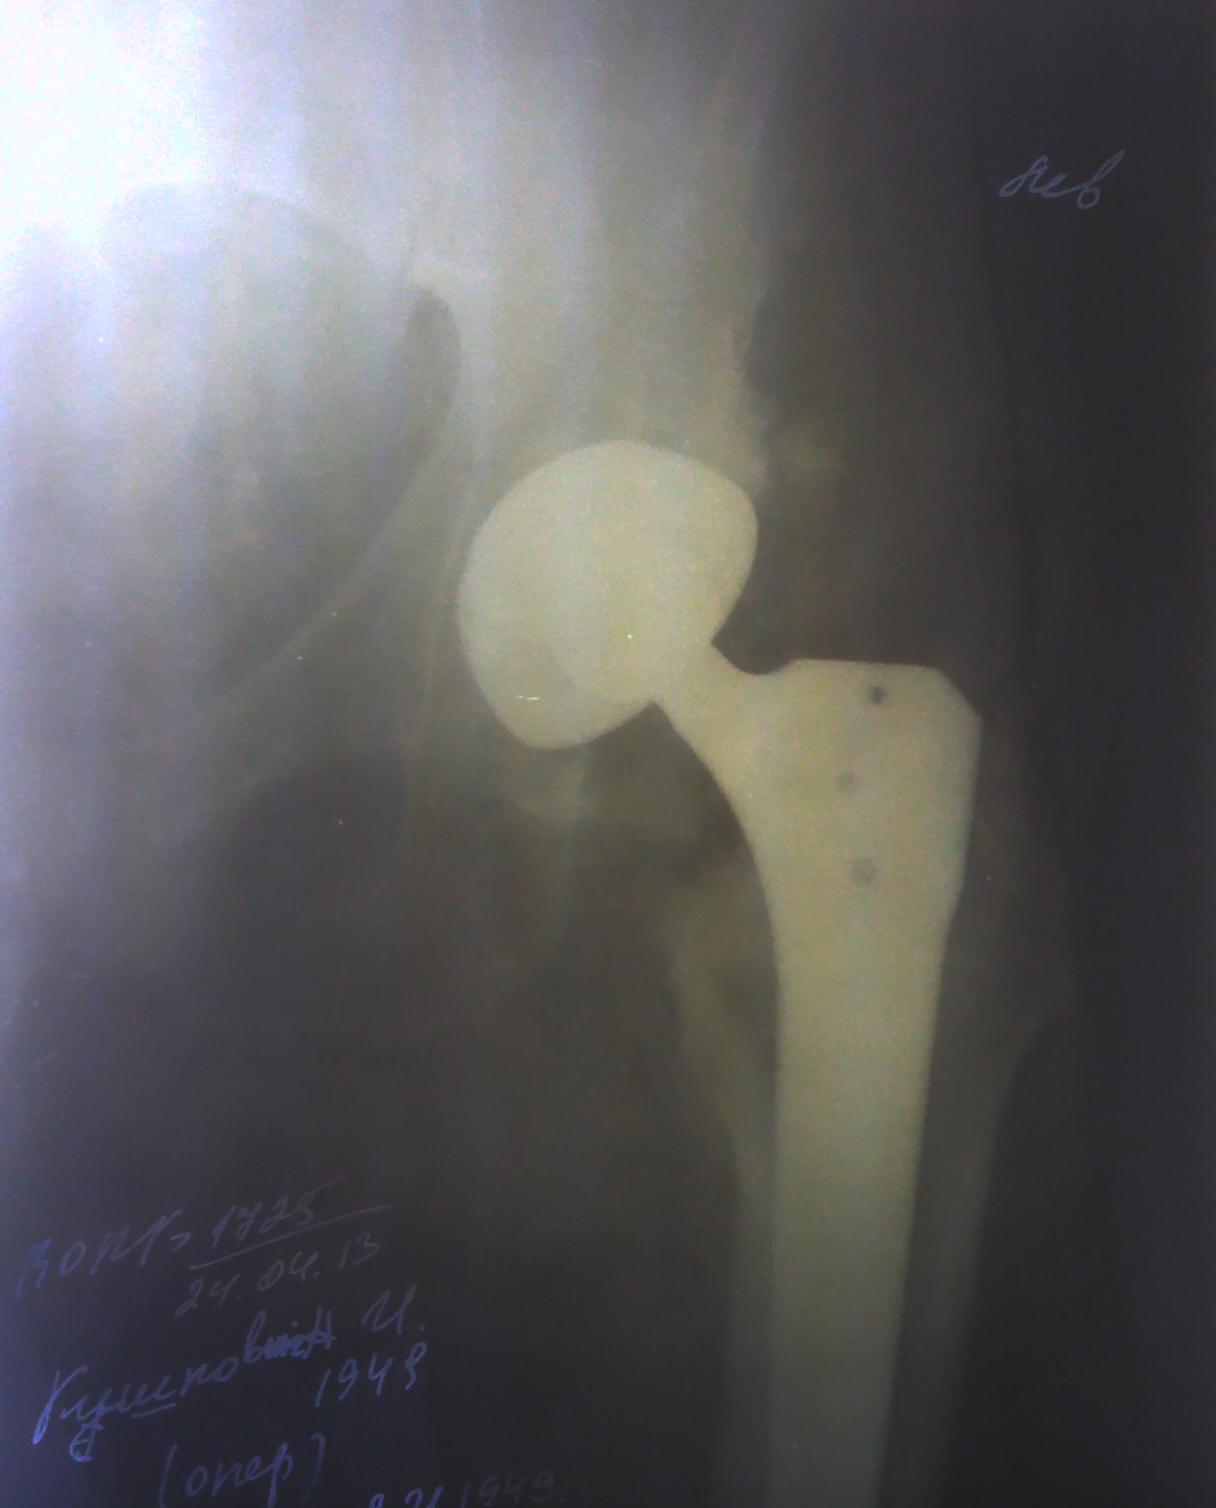

Тотальное эндопротезирование левого тазобедренного сустава: под спинномозговой анестезией в положении больного на спине произведен доступ в области сустава. Выполнена остеотомия шейки бедра, удалена головка бедра. В образованную впадину, установлена чашка №55 с вжатием. В бедренной кости установлена ножка №7. Головка (L). Протез выправлен. Гемостаз и промывание раны по ходу операции. Дренирование. Послойные швы. Асептическая повязка.

Rtg левого тазобедренного сустава от 24.04.13г.:

На прицельной послеоперационной Rtg-грамме левого тазобедренного сустава определяется состояние после тотального эндопротезирования. Соотношение суставных поверхностей правильное.